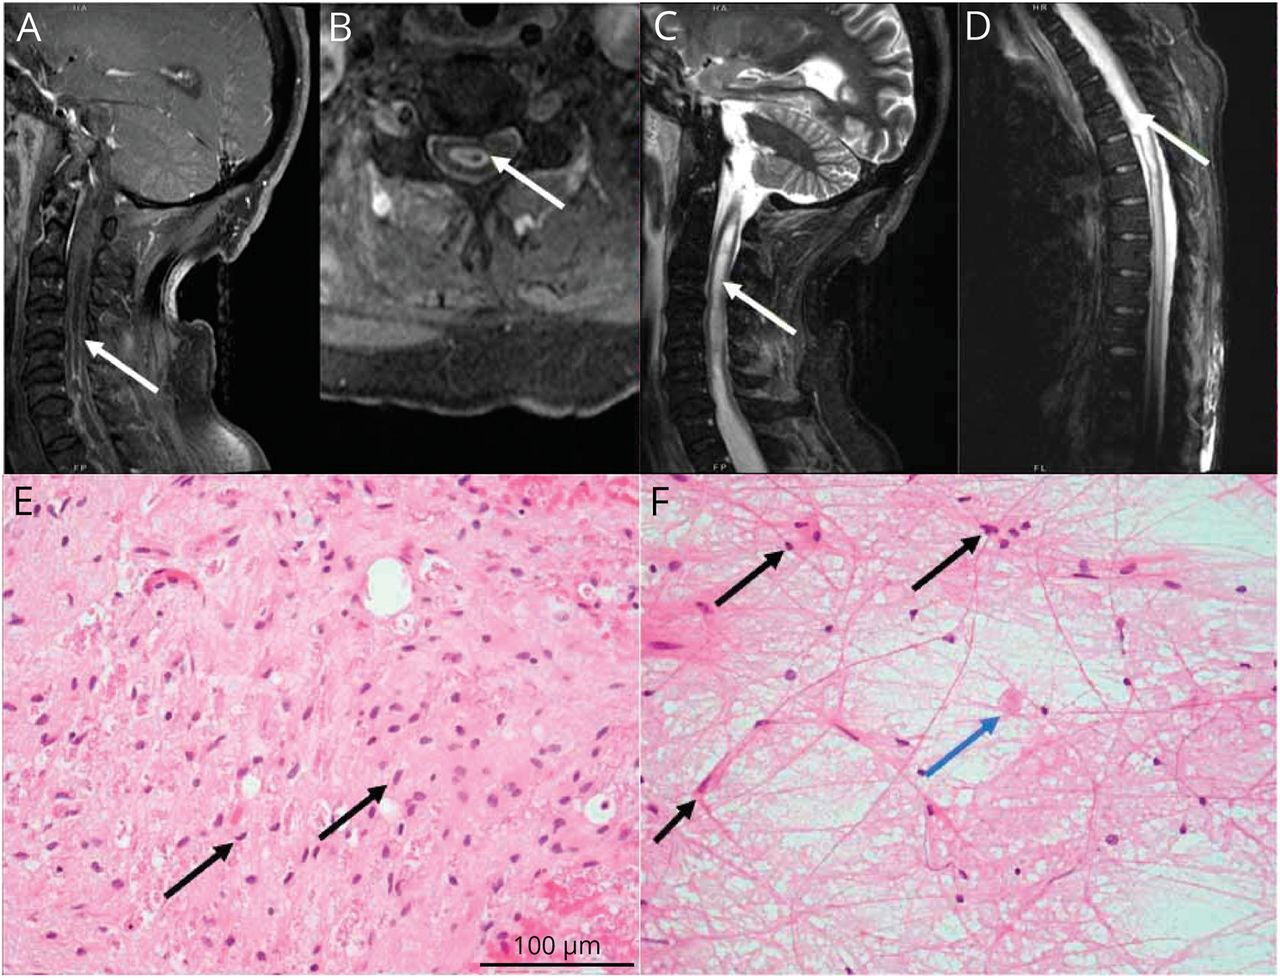

脊柱MRI显示一个扩大的,髓内T2 hyperintense信号异常,与周边结节增强跨越C4-T5 (A, B)和纵向广泛扩张T11 obex的中央管(C, D)。)部分在400×放大显示浸润神经胶质瘤与适度多形性,深染细胞与piloid流程(E, F黑色箭头)和偶尔的嗜酸性颗粒体(F,蓝色箭头)。他走时=苏木精和伊红。

一个68岁的男人没有病史发达的进步的软弱和cervicalgia 2个月。检查显示与T10感官层面的四肢瘫痪。脊柱MRI显示obex的膨胀性的髓内病变与周围结节性增强(T11图中,模拟)。大脑核磁共振、全身PET / CT和广泛的血清诊断是正常的(eTable 1,links.lww.com/WNL/C653)。脑脊液显示蛋白质2505 mg / dL, 0细胞/μL葡萄糖88 mg / dL,脑脊液细胞游离DNA测序中分离出一种致病变种叔p。神经胶质瘤C250T,可疑。1胸脊髓切片是追求排气可逆的病因和显示浸润神经胶质瘤叔启动子突变(图中,E和F)。由于进行性四肢瘫痪、呼吸衰竭,预后差,护理是为了安慰。